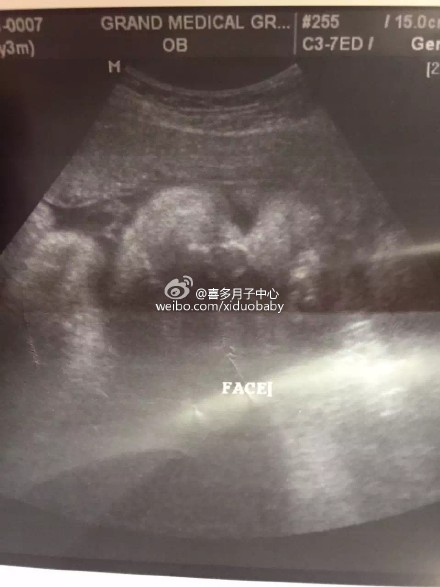

【孕妇妈妈对美国医生医院的评价】入住在洛杉矶喜多月子中心Rancho cucamonga别墅的北京赴美生子孕妈最近来到医院进行产检,并知晓了宝宝的性别,是个小男生,妈妈对美国这边的服务以及设施等方面都很满意,很安心顺畅的美国生子之行,祝妈妈一切顺利!